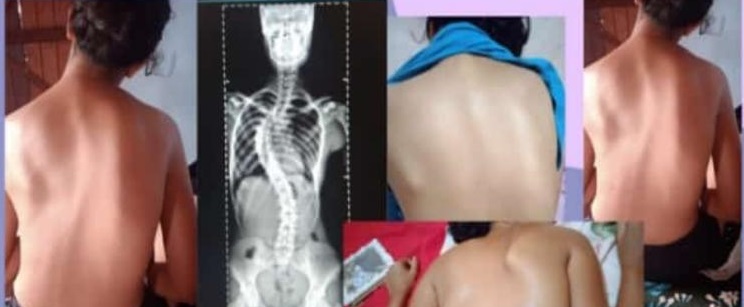

Uma mãe desesperada em Ourolândia, município da região de Jacobina, está fazendo um apelo dramático por ajuda para a realização de uma cirurgia para sua filha adolescente, diagnosticada com escoliose em grau avançado. Tânia Márcia Lima dos Santos, moradora da localidade de Alazão, está buscando recursos para custear a cirurgia de Yasmyn Santos Silva, de 16 anos, já que na rede privada o procedimento pode variar entre R$ 20 mil e R$ 150 mil, dependendo da gravidade do caso.

A família de Yasmyn enfrenta dificuldades devido à falta de estrutura médica especializada na região de Jacobina, o que os levou a recorrer às redes sociais em busca de apoio. Em um relato emocionado, Tânia Márcia descreve a jornada de sua filha, desde as queixas de dor na infância até o diagnóstico de uma curvatura acentuada na coluna vertebral. A família buscou atendimento médico e realizou exames, constatando a necessidade urgente da cirurgia.

A situação de Yasmyn se agrava a cada dia, com dores intensas e problemas respiratórios decorrentes da curvatura em sua coluna. Tânia Márcia relata as idas frequentes ao hospital, os medicamentos fortes utilizados e a falta de eficácia dos tratamentos. Como mãe, ela expressa seu desespero diante da situação e faz um apelo para que alguém com contatos ou influência possa agilizar o processo cirúrgico.